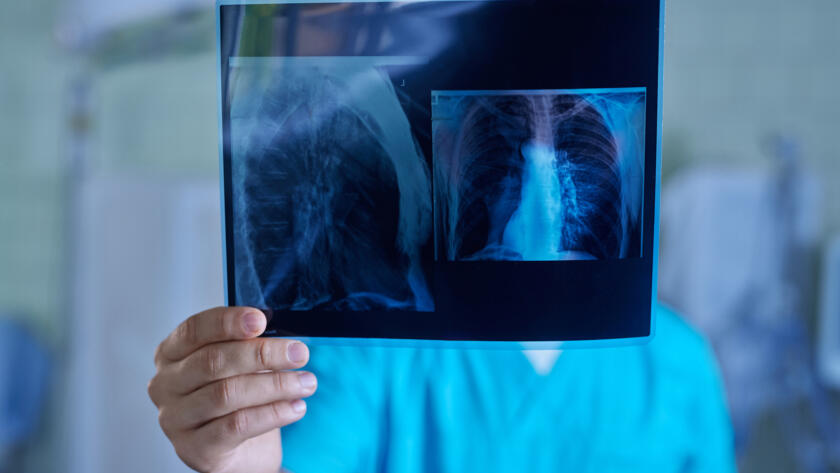

Günümüzde check-up (tarama) programlarının ve bilgisayarlı tomografinin (BT) yaygınlaşmasıyla birlikte, “akciğerde nodül” (halk arasındaki tabiriyle akciğerde leke) saptanma oranı oldukça artmıştır. Polikliniklere başvuran hastaların en büyük endişesi, raporda gördükleri bu…